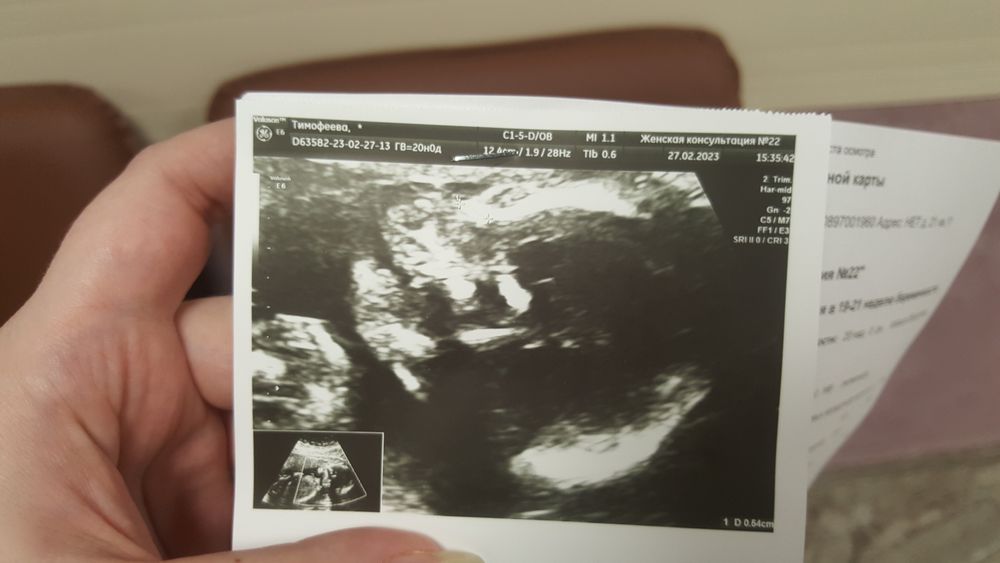

2скр на память 🐣

Сегодня прошли 2скр. Теперь мои нервы спокойны 😉 Около 40 минут врач мяла мне живот (думала, будет синяк 😊) т.к. дочь не хотела поворачиваться лицом к датчику.

Ттт все отлично 🤗 Лежит головой вниз, всем нормам соответствует, все без аномалий. Только вот опережает рост на 5 дней... Врач посоветовала соблюдать жесткую диету, иначе, по ее словам, есть риск, что ребенок родится 4 кг.

Фото не прикрепилось - тут, видимо, воды глотает, рот открыла 😋